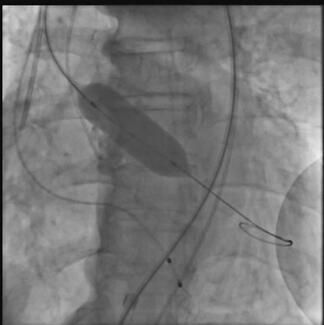

Jha Manvendu, DrNB; G. Keshavamurthy, DM

Department of Vascular Surgery, Army Hospital Research & Referral, New Delhi, India

A 74-year-old man, who was a chronic smoker with a known case of hypertension and chronic obstructive pulmonary disease, presented with a history of breathlessness on minimal exertion.